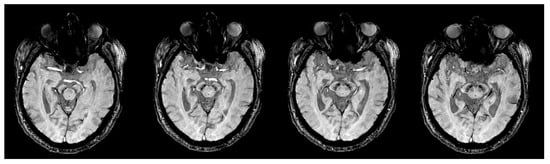

- Schwarz, S.T.; Mougin, O.; Xing, Y.; Blazejewska, A.I.; Bajaj, N.; Auer, D.P.; Gowland, P. Parkinson’s disease related signal change in the nigrosomes 1–5 and the substantia nigra using T2* weighted 7T MRI. NeuroImage Clin. 2018, 19, 683–689. [Google Scholar] [CrossRef]

- Schwarz, S.T.; Afzal, M.; Morgan, P.S.; Bajaj, N.; Gowland, P.A.; Auer, D.P. The ‘swallow tail’ appearance of the healthy nigrosome—A new accurate test of Parkinson’s disease: a case-control and retrospective cross-sectional MRI study at 3T. PLoS ONE 2014, 9, e93814. [Google Scholar] [CrossRef] [PubMed]

- Schwarz, S.T.; Xing, Y.; Naidu, S.; Birchall, J.; Skelly, R.; Perkins, A.; Evans, J.; Sare, G.; Martin-Bastida, A.; Bajaj, N.; et al. Protocol of a single group prospective observational study on the diagnostic value of 3T susceptibility weighted MRI of nigrosome-1 in patients with parkinsonian symptoms: the N3iPD study (nigrosomal iron imaging in Parkinson’s disease). BMJ Open 2017, 7, e016904. [Google Scholar] [CrossRef]